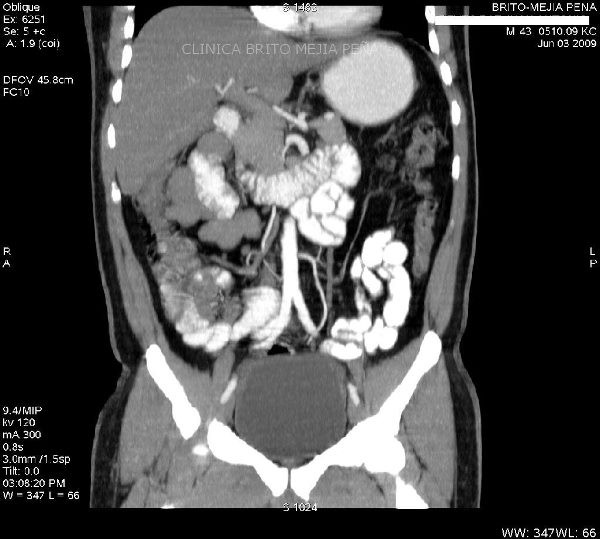

Plastron apendicular